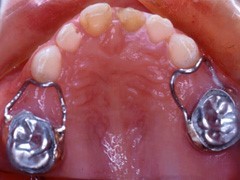

在混合齒列期中,維持將來永久牙長出時所需要的空間,也是乳牙存在的重要性之一。不幸的是,往往有許多的原因使得乳牙提早脫落,造成乳牙維持空間的功用消失。而使乳牙提早脫落的原因通常有:因為蛀牙太大,導致乳牙需要被拔除;因為意外創傷而使乳牙提早脫落;因為永久牙太大或異位生長而造成旁邊乳牙提早脫落;治療失敗的乳牙,需要提早被拔除…等等。

一旦乳牙提早不存在時,我們若沒有及時做好適當處理的話,這些寶貴的空間就會因後牙的前傾移動,而造成萌牙空間的消失;於是將來小孩齒列提早掉落後,需要採取何種適當的防範措施,使得將來牙齒萌長空間不足的機會大大地減低,或者縮短將來需要做矯正治療的過程及時間,甚至完全免除小孩牙齒矯正的需要?空間維持器就是我們的答案了。